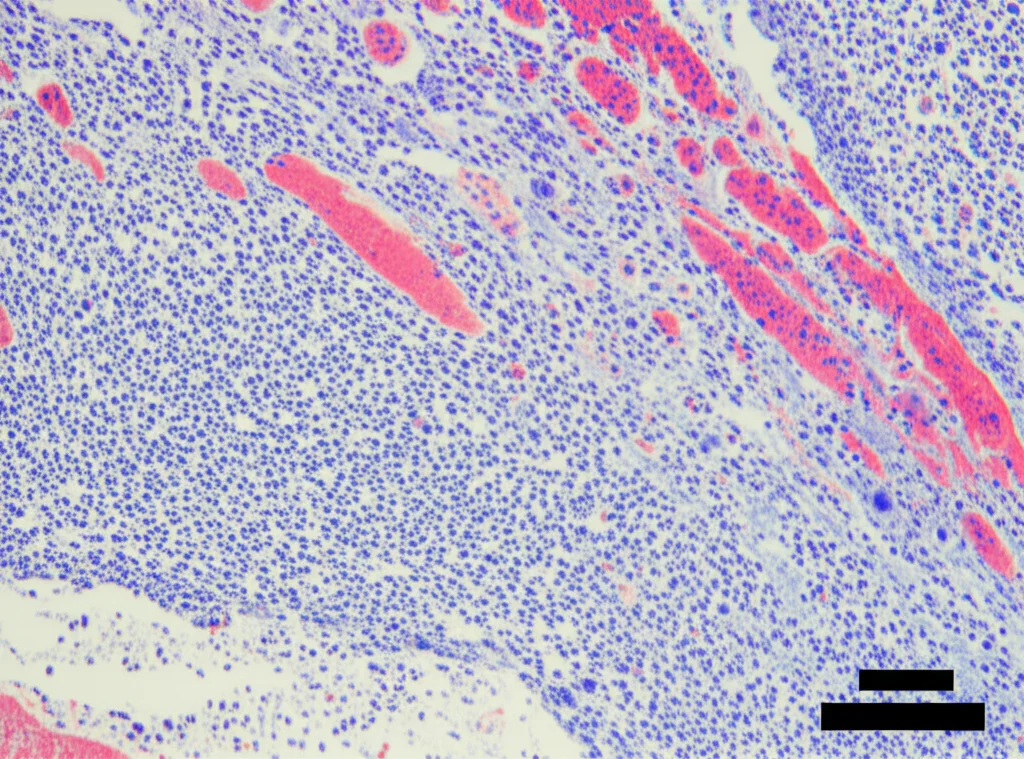

Dopo 4 e 8 settimane dall’intervento, abbiamo analizzato la quantità e la qualità del nuovo osso formato usando la micro-CT (una specie di TAC ad altissima risoluzione) e l’analisi istologica (osservando fettine sottilissime di tessuto al microscopio).

L’analisi istologica ha confermato questi dati: nel gruppo LV-CA1 + Co-coltura abbiamo osservato molto più osso neoformato, con trabecole ossee (le “impalcature” interne dell’osso) più dense e interconnesse e più collagene immaturo (segno di attiva deposizione di matrice ossea), rispetto agli altri gruppi.